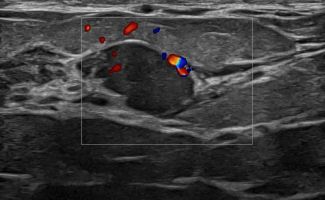

Modern ultrasound machines, equipped with advanced high-frequency transducers, techniques such as Color Doppler, Power Doppler, B-Flow, and Elastography, allow the analysis of breast architecture with exceptional accuracy.

Elastography can highlight the elasticity of a lesion, indicating whether it is hard or soft. Through this technique, we can assess the nature of the lesion, providing indications of whether it is benign or malignant. Additionally, with the contribution of Color Power Doppler and B-Flow, we can monitor the vascular flow within the lesions, offering even more information about the type and nature of the abnormality.